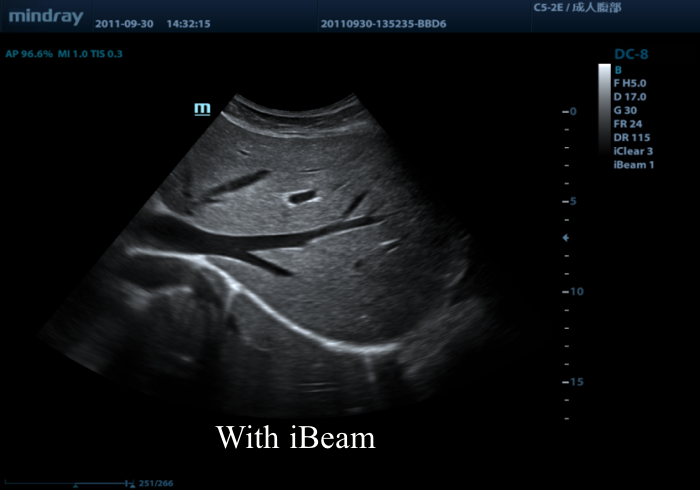

Предлагаем вам ознакомиться с примером применения данной технологии. Изображения выполнены на приборе Mindray DC-8, на верхнем изображении режим iBeam (компаундинг) отключен, а на нижнем включен на первую ступень регулировки (3 луча).

14.png

15.png